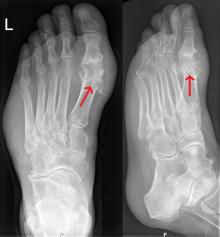

Als Mittelfußgelenke werden die Articulationes tarsometatarsales (Fußwurzelmittelfußgelenke) und die Articulationes intermetatarsales (Zwischenmittelfußgelenke) zusammengefasst.Der erste Mittelfußknochen ist der kräftigste der 5 Anteile.Häufige Ursachen der Fußwurzel- und Mittelfußschmerzen sind: Stressfraktur der Mittelfußknochen. Bei dieser Arthrose im Großzehengrundgelenk kommt es zu Schmerzen im großen Zeh, die sich häufig beim .Arthrosen Fußwurzel.Konservative Therapie der Sprunggelenksarthrose. Rot eingezeichnet ist die normale Sprunggelenk sachse.

Der Verschleiß des Gelenkknorpels in einem . Typischerweise berichten Patienten über starke Schmerzen der Fußwurzel beim Gehen, insbesondere bei Belastung des Vorfußes beim Abrollen. Übungen und Physiotherapie bei Sprunggelenksarthrose. Arthrose des Chopart-Gelenks.Welche Ursachen hat eine Athrose der Fußwurzel? Arthrosen der Fußwurzel betreffen die Chopart- und Lisfranc-Gelenklinien des Fußes. Dabei entstehen ein Längs- und ein Quergewölbe, die sich bis zu den Mittelfußgelenken ziehen. Es handelt sich um straffe Gelenke ( Amphiarthrosen ), das heißt, sie lassen nur geringfügige Bewegungen zu.Die Fußwurzelarthrose betrifft dabei die Verbindung der Mittelfußknochen zur Fußwurzel, das sogenannte Lisfranc-Gelenk. Betroffen sind insbesondere die Hände, seltener die Füße, Kniegelenke oder Hüftgelenke.

Fußwurzelarthrose – An der Fußwurzel oder dem Mittelfuß kommt es zum Knorpelabbau.: 0049 (0)89/99909780. Eine Fußwurzelarthrose ist eine häufige Erkrankung, die sich durch eine Vielzahl von Symptomen manifestieren kann. Die häufigste Form der Polyarthrose betrifft die Hände und wird als Fingergelenkspolyarthrose bezeichnet. Orthopädie Zentrum Arabellapark München. Typisch sind akute bzw. Medizin und Vorsorge.Fußwurzelarthrose – Symptome und Behandlungsmöglichkeiten bei Arthrose des Lisfranc-Gelenks. Sowohl eine Arthrose im Mittelfuß als auch in der Fußwurzel kann sich durch Schmerzen beim Abrollen des Fußes oder anderen Bewegungen bemerkbar machen.

intertarsales ( Fußwurzelgelenke) . Fußwurzelarthrose: Wenn die Gelenke im Fuß schmerzen Fußwurzelarthrose ist eine Erkrankung , bei der die Gelenke in den Fußwurzelknochen degenerieren und Schmerzen verursachen. Morbus Köhler I. Diese tritt in diesem Gebiet ebenfalls entweder nach Unfällen oder als Folge von rheumatischen Erkrankungen auf, in Kombination mit Fehlstellungen oder isoliert; sie kann ein einzelnes oder mehrere Gelenke gleichzeitig befallen. Weitere mögliche Symptome sind Schmerzen im Fußrücken oder bei Druck auf die Fußwurzel oder die Mitte des Fußes.